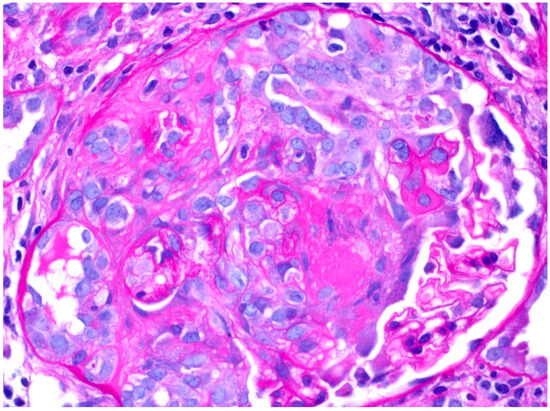

2. Case Presentation